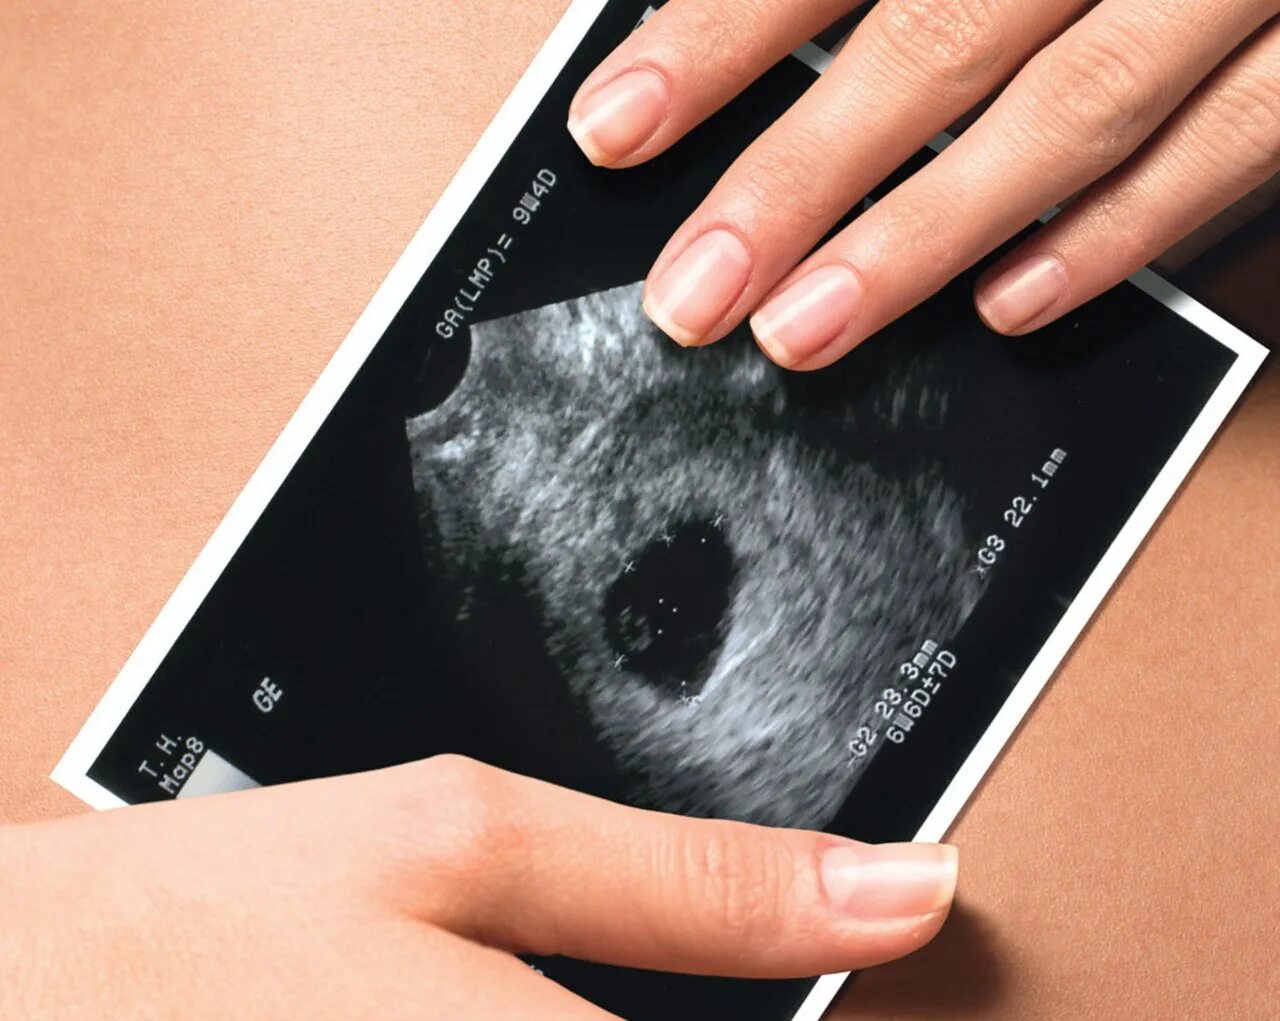

Белое пятно на узи